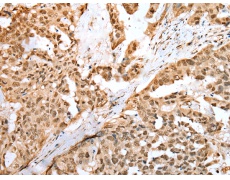

IHC positive control: |

Human breast cancer and human thyroid cancer |